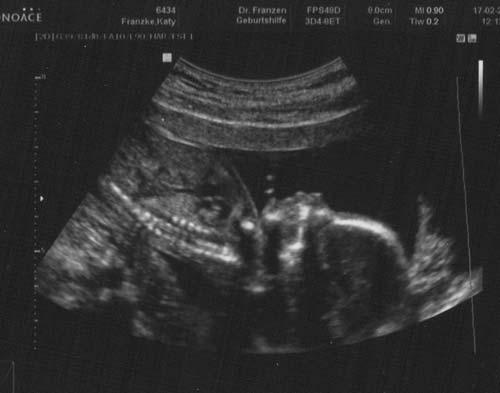

Habe ein niedliches Babyfoto mitbekommen,schaut mal..habt ihr auch sollche Bilder?

Den, unserem Mädchen heute zu 100% bestättigt geht es richtig gut. Bei der U.Untersuchen hat sie fröhlich getretten, Wasser geschluckt und Pipi gemacht.Den anfangs der Untersuchung war Babyblase voll, und zum Ende war sie leer

Die größe der kleinen ist ungefähr 18cm ssl. konnte man schlecht messen.